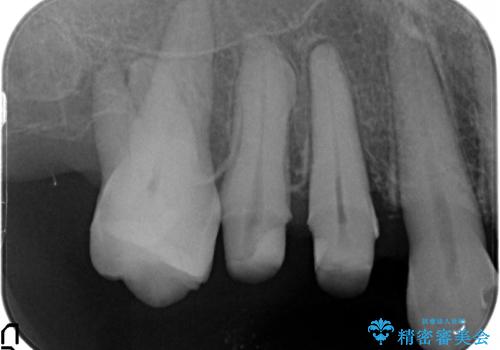

部分矯正を含む 歯周病治療 (再生治療・歯周ポケット除去・MTM・連結補綴)

検査の結果、強い歯ぎしりによる歯の周囲の骨の吸収が認められたため歯槽骨の再生・歯周ポケットの除去・力に対抗する連結補綴・補綴前処置としての小矯正を計画します。

特定の歯に強く力がかかりまた歯周病により臨床歯根が短くなっているような場合、歯の動揺を抑えるため連結補綴が検討されます。

歯の動揺が続くとより周囲の骨を失い最終的には歯を喪失してしまう可能性が高くなってしまうためです。

今回連結補綴を行うにあたり、歯周病の問題を解決するために再生療法・歯周ポケット除去手術を、またより歯の神経を保存し力に対抗できる環境を整えるために小矯正を行い精度の高いメタルボンドクラウンを製作することができました。